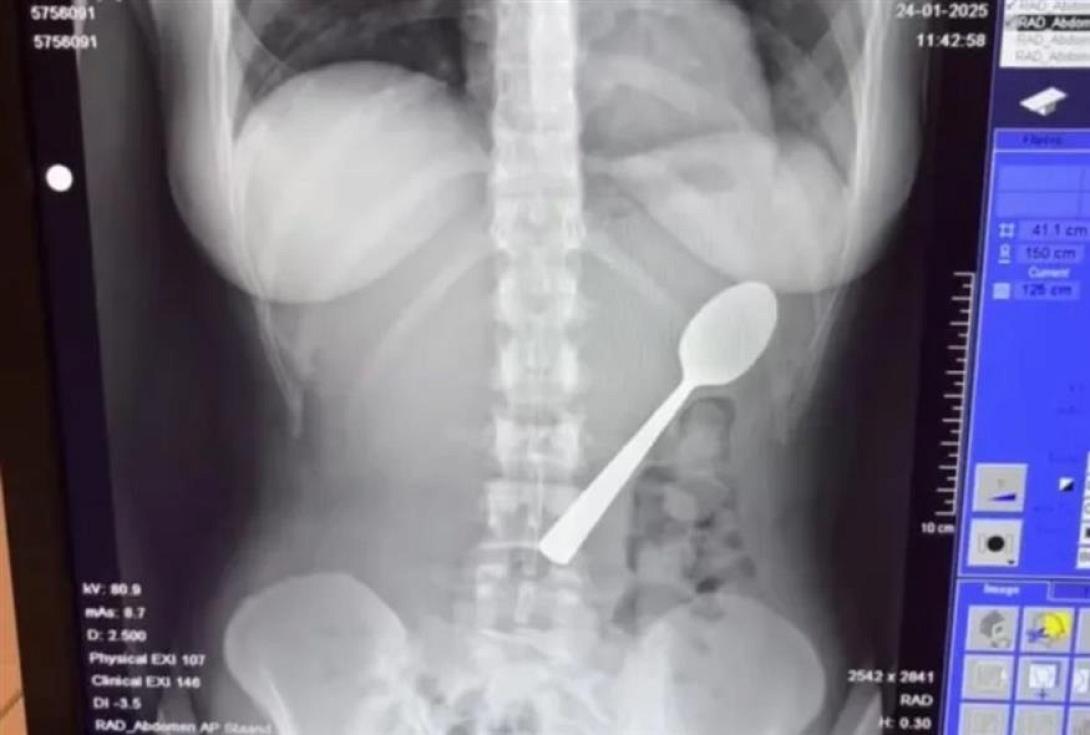

Η Ρέιμι Άμελινξ δεν το έκανε, το κράτησε στο στόμα της περισσότερη ώρα για να απαντήσει σε ένα μήνυμα και βρέθηκε να καταπίνει ένα κουτάλι 17 εκατοστών, μια εμπειρία διόλου ευχάριστη αν και η ίδια παραδέχθηκε ότι «γλίστρησε πολύ ομαλά στο στομάχι μου».

Οι γιατροί της είπαν ότι το κουτάλι ήταν πολύ μεγάλο για να βγει... φυσιολογικά, οπότε έπρεπε να επιστρέψει σπίτι και να περιμένει μέχρι να προγραμματιστεί γαστροσκόπηση.

Η Reymy είπε: «Εκείνη η νύχτα ήταν δύσκολη, ένιωθα το κουτάλι να κινείται, μερικές φορές ακόμη και ανάμεσα στα πλευρά μου.

Ήταν πραγματικά τρομακτικό. Ένιωθα φουσκωμένη, είχα ναυτία και κάθε φορά που έτρωγα κάτι, ένιωθα περίεργα. Ήταν δύσκολο να κοιμηθώ, γιατί κάθε στάση μου θύμιζε το κουτάλι στο στομάχι μου».